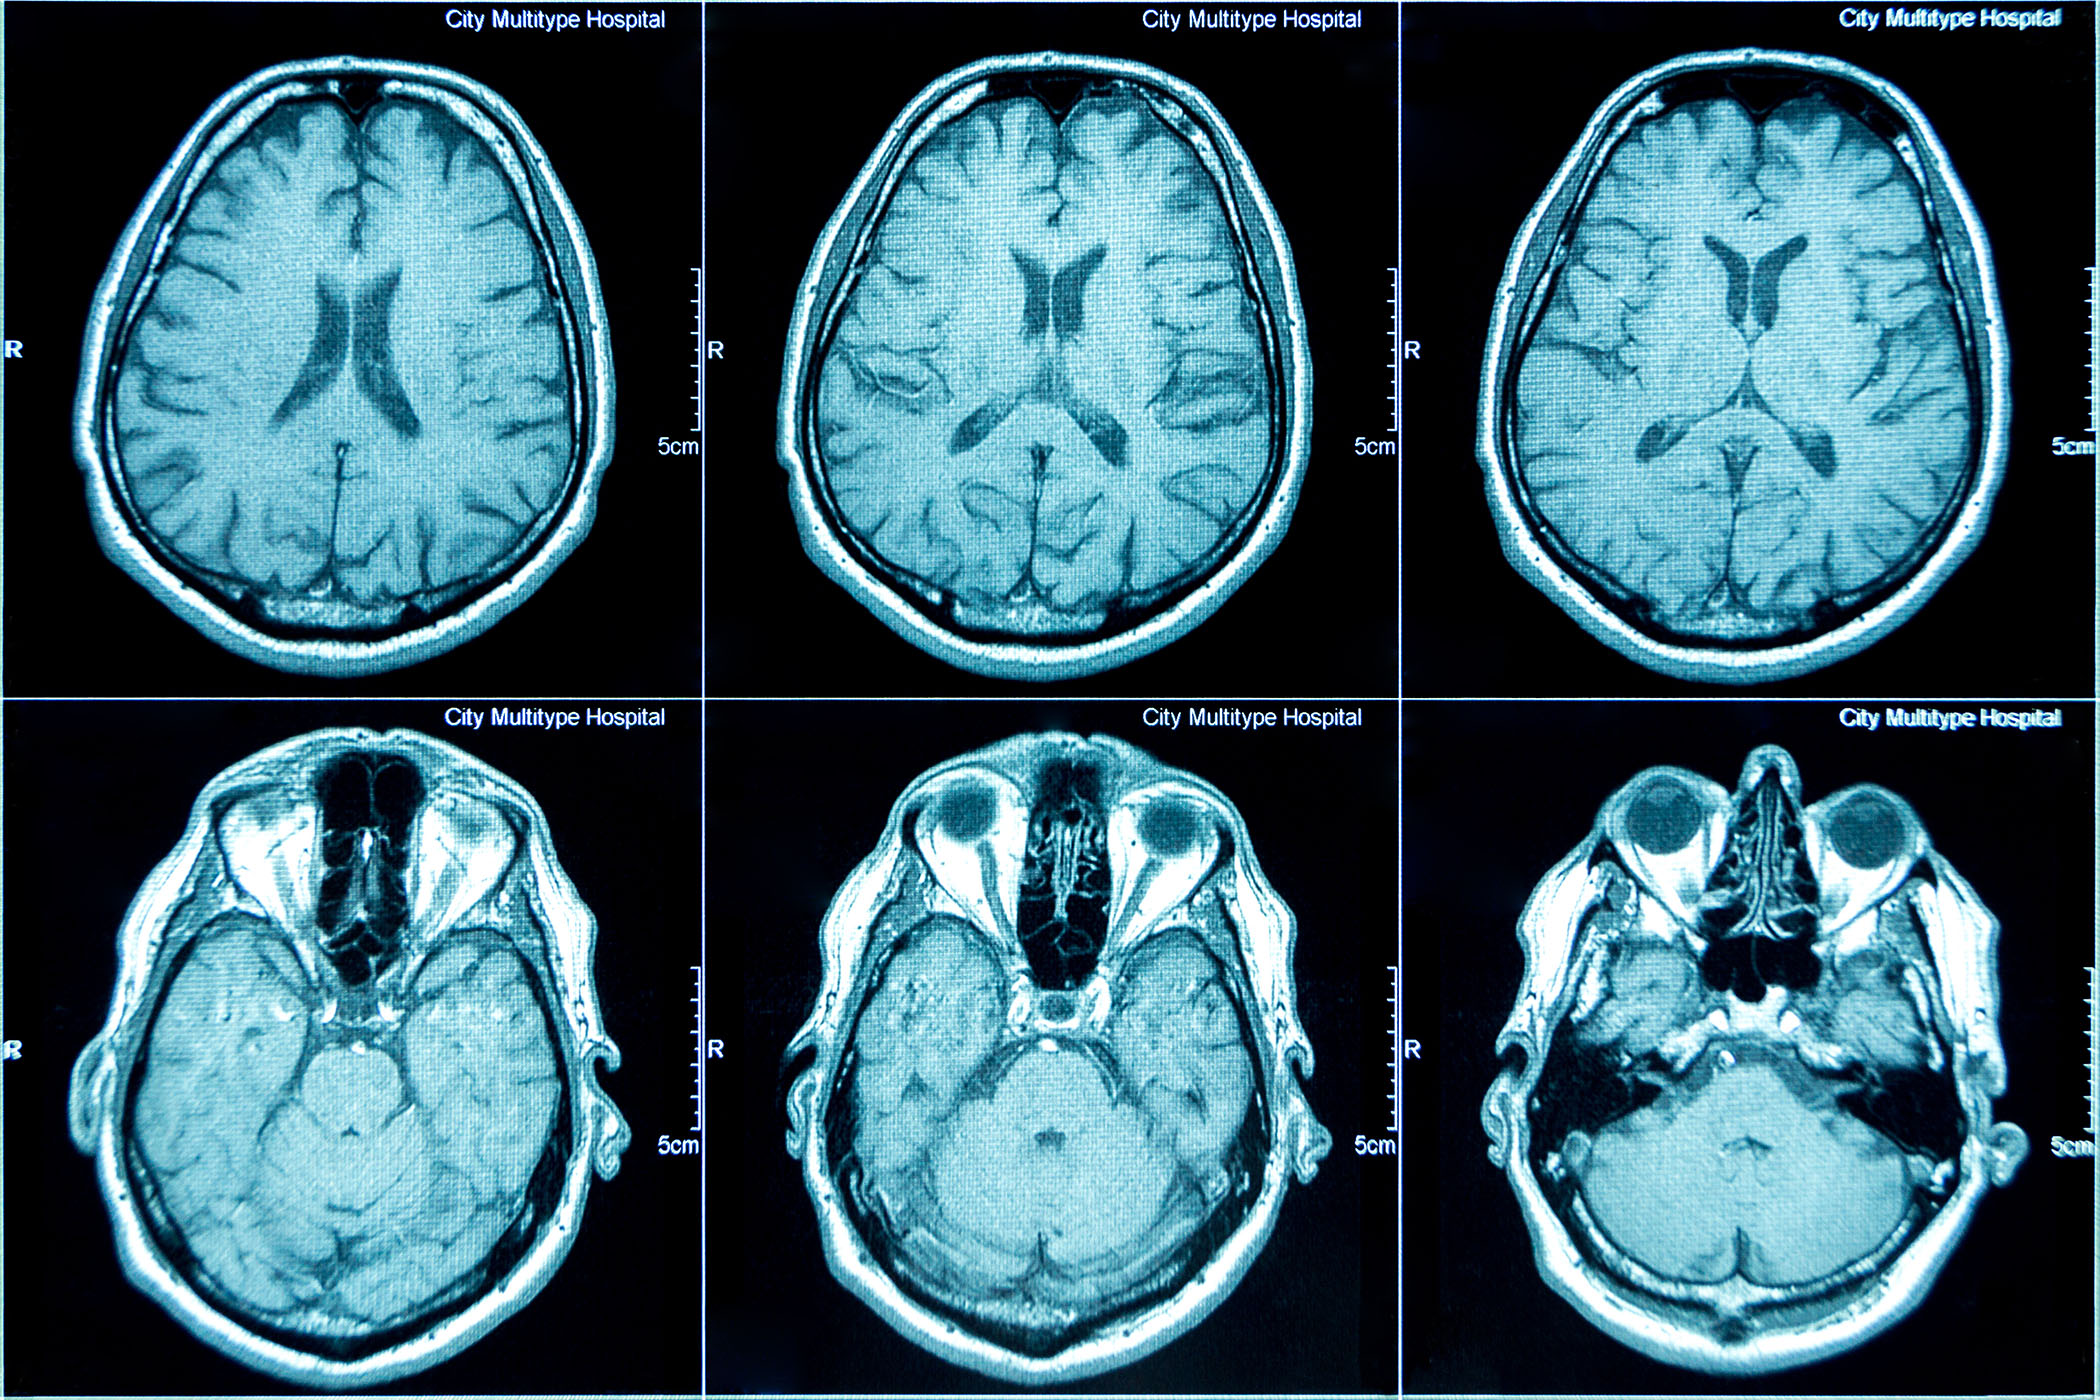

The findings show that witnessing abusive leadership first activates motivational brain regions, including the insula and cingulate cortex, associated with emotional salience, anger and alarm.

As observers move from watching the interaction to evaluating it, neural activity shifts toward regions linked to empathy, social cognition and moral reasoning, such as the superior temporal gyrus, fusiform gyrus and anterior cingulate cortex. Rutgers researchers said this pattern suggests that third-party reactions unfold in stages, beginning with emotional arousal and transitioning into reflective moral judgment.